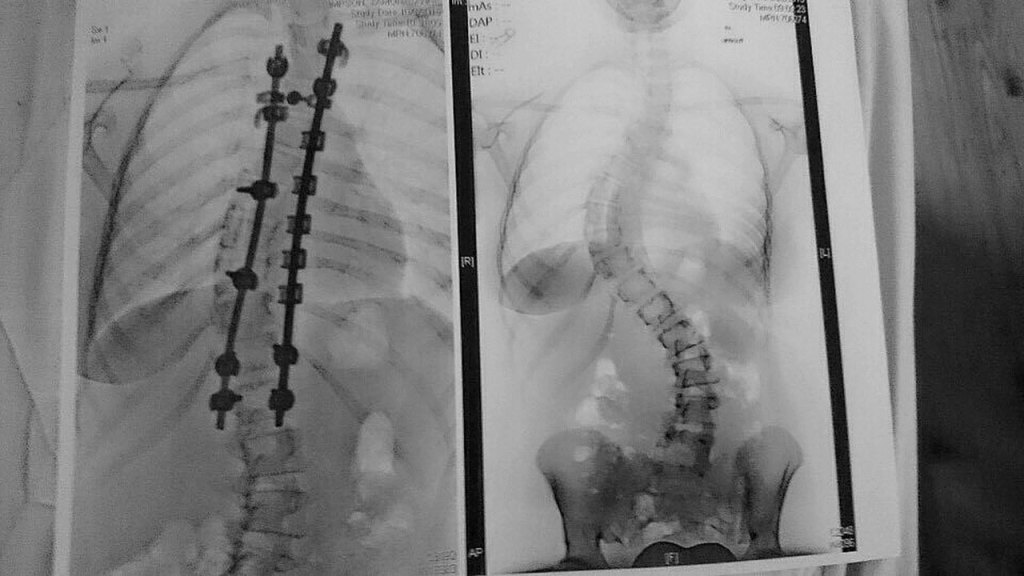

The then-15-year-old’s May 2016 diagnosis revealed her spine looked like an “S” with a 75-degree upper curve to the right and a 45-degree lower curve to the left.

During the four months she waited to have her back surgery, her spine’s curvature got worse by 10 degrees bringing the top curve to 85 degrees, a significant change in such a short amount of time. Simpson had decided to run track her last quarter of school, but running soon became painful.

In a six-hour surgery, doctors at Seattle Children’s Hospital used two rods and several screws to align her spine to become straighter. Doctors also used bone graft tissue from Renton-based LifeNet Health to promote bone growth in the areas where the screws were.